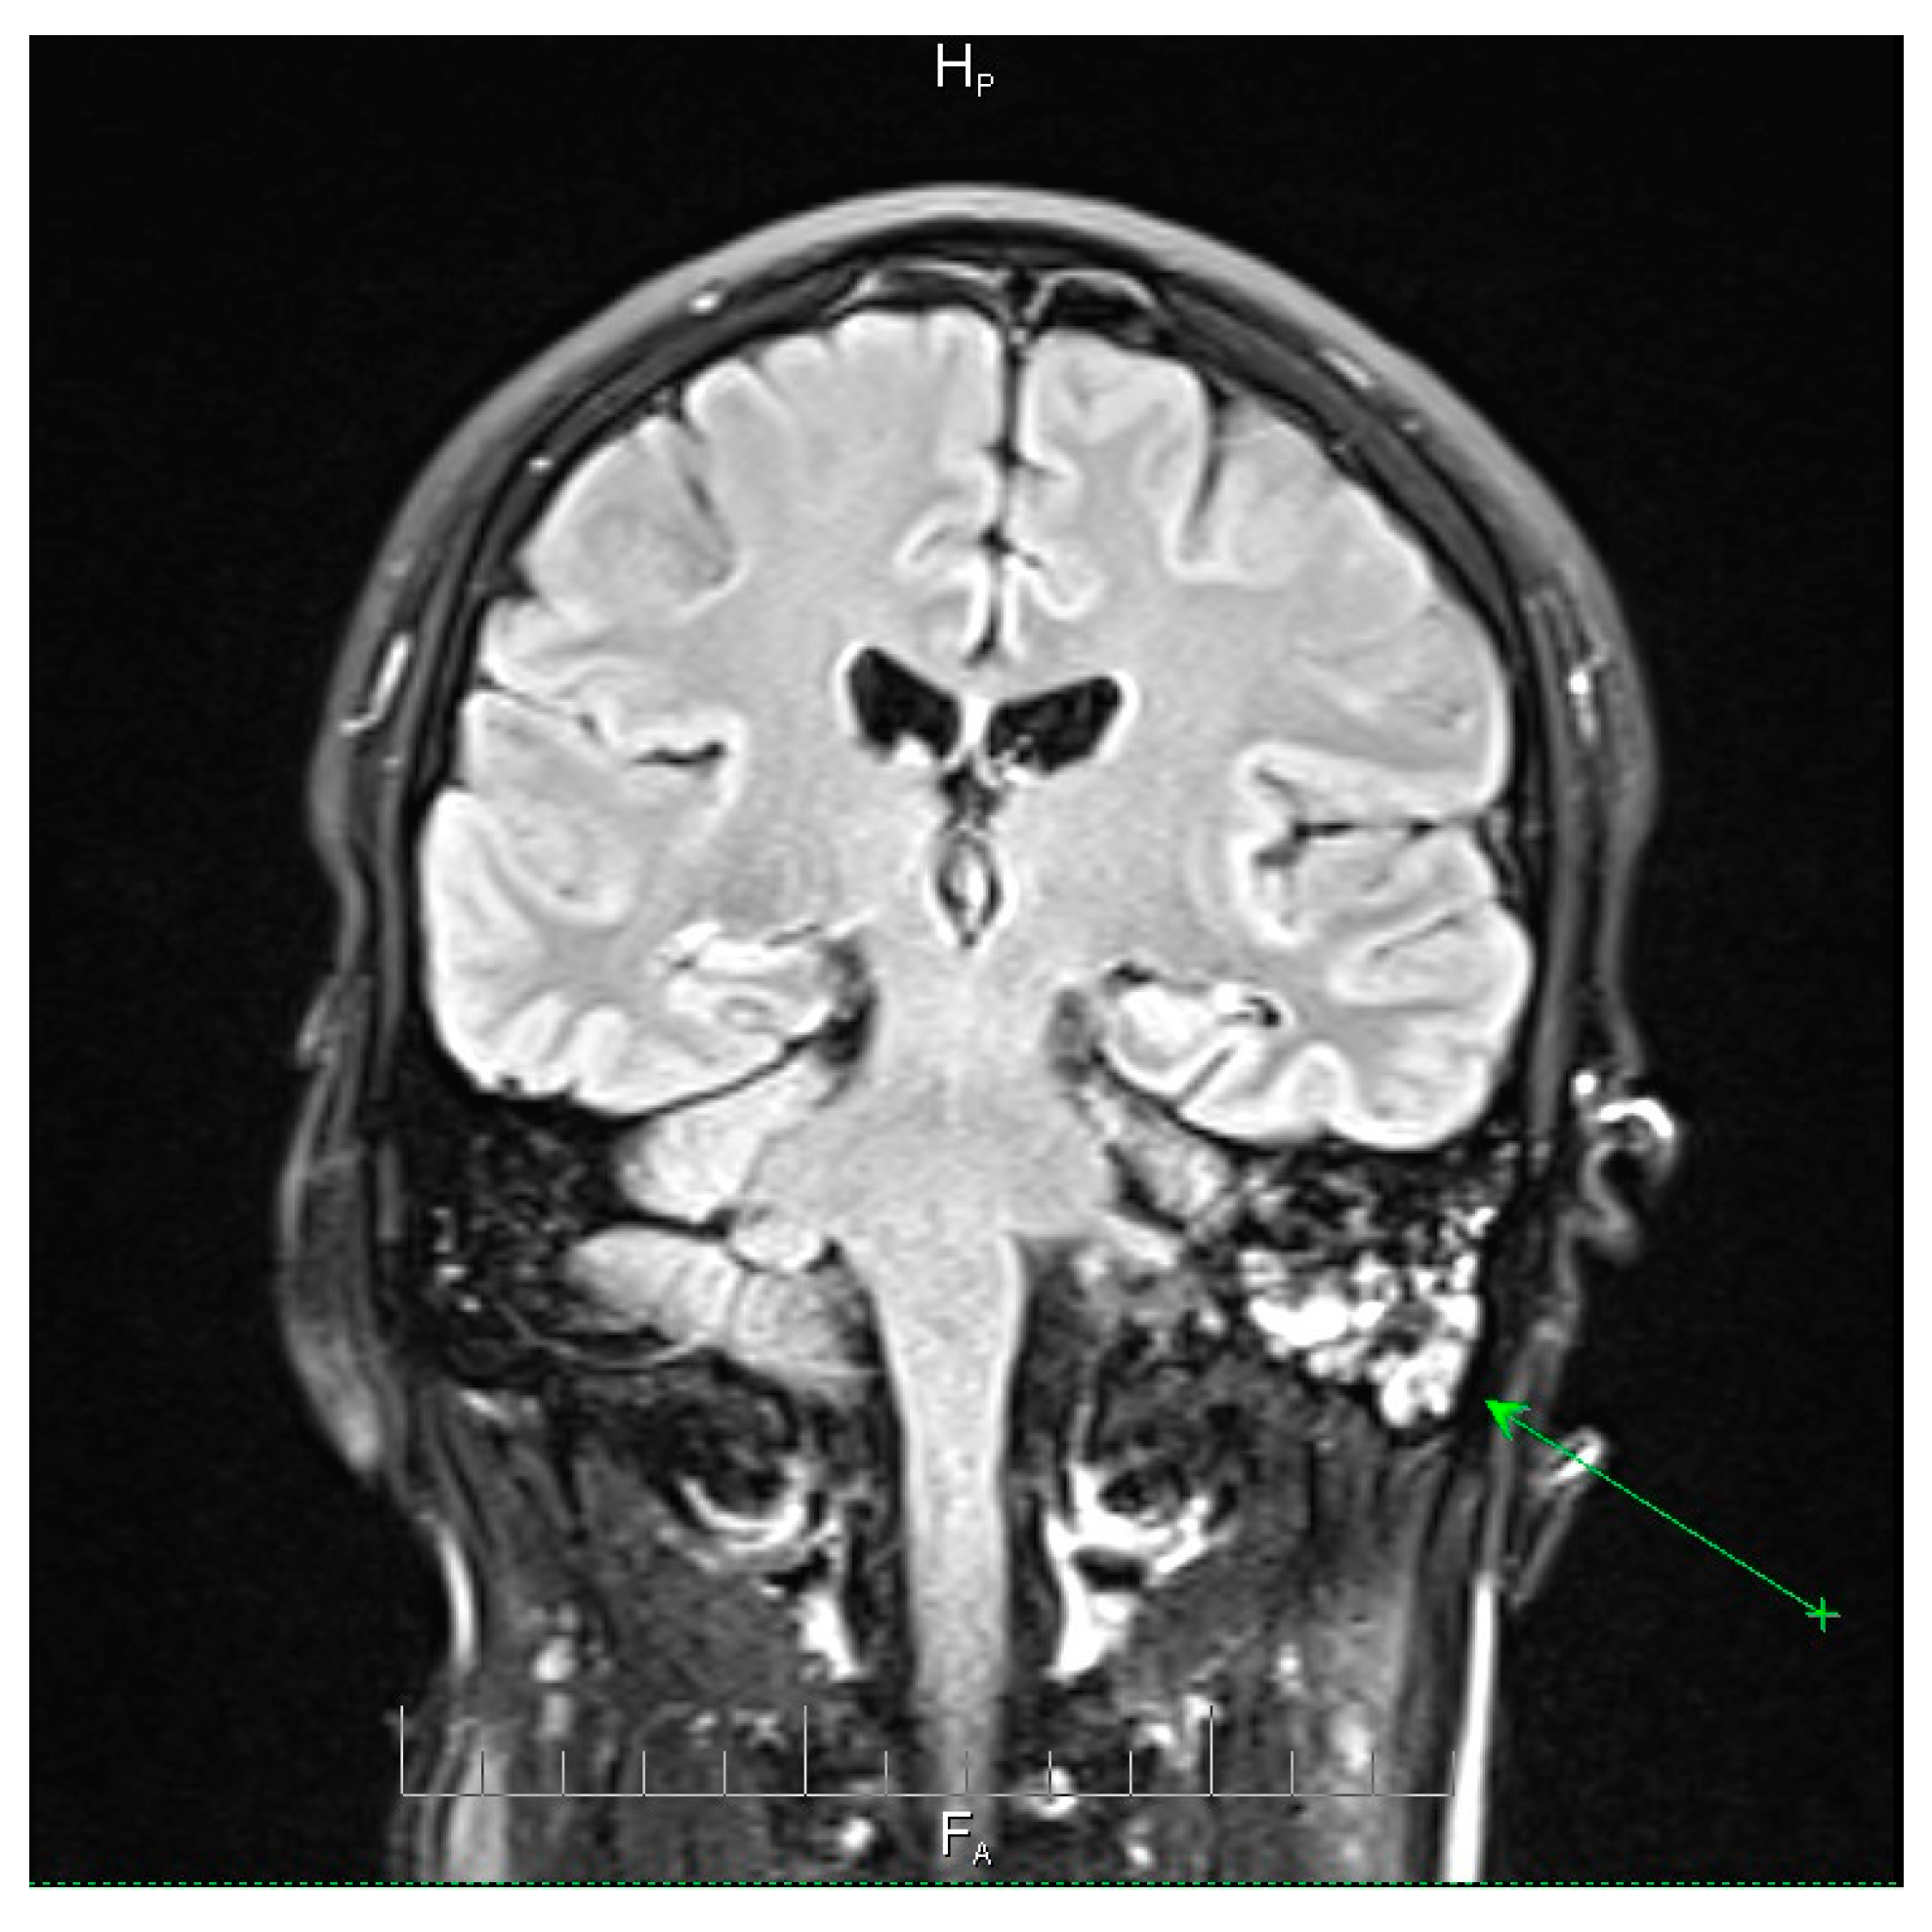

Figure 3.

Axial T2-weighted MRI scan demonstrating the post-septoturbinoplasty reduction status on the right. Mild inflammatory changes were observed in the mucosa of the maxillary sinuses, predominantly on the left side, with less pronounced involvement of the ethmoidal cell system. No evidence of acute intracranial pathology or parenchymal lesions was observed. These findings indicate residual postoperative changes and mild sinonasal inflammation, providing context for the patient’s clinical presentation and helping to differentiate postoperative alterations from active infectious processes. AH = anterior-head. PF = posterior- foot. Axial T2-weighted MRI scan demonstrating the post-septoturbinoplasty reduction status on the right. The green arrow indicates a focal area of mucosal thickening and fluid signal within the left maxillary sinus, consistent with mild inflammatory changes, with less pronounced involvement of the ethmoidal cell system. No evidence of acute intracranial pathology or parenchymal lesions was observed. These findings indicate residual postoperative changes and mild sinonasal inflammation, providing context for the patient’s clinical presentation and helping to differentiate postoperative alterations from active infectious processes.